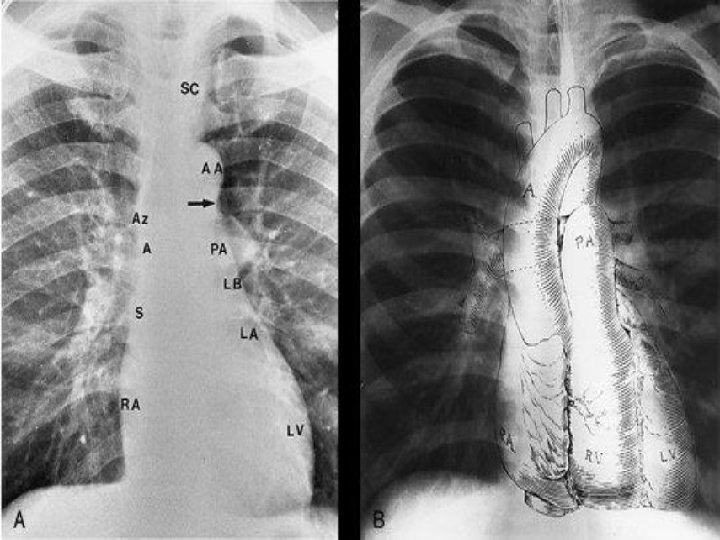

� Au niveau du bord droit , on décrit : un arc supérieur et un arc inférieur. 1 - L’arc supérieur droit, rectiligne ou légèrement concave, est constitué du tronc veineux brachiocéphalique et de la veine cave supérieure. 2 - L’arc inférieur droit, convexe, est constitué du bord latéral de l’oreillette droite et de la veine cave inférieure. � Au niveau du bord gauche , on décrit 3 arcs : supérieur gauche, moyen gauche et inférieur gauche. 1 - L’arc supérieur gauche correspond à l’artère subclavière gauche et à la portion horizontale de la crosse aortique(le bouton aortique). 2 -L’arc moyen gauche correspond au tronc de l’artère pulmonaire dans ses 2/3 supérieurs et à l’auricule gauche dans son 1/3 inférieur. 3 -L’arc inférieur gauche correspond au ventricule gauche